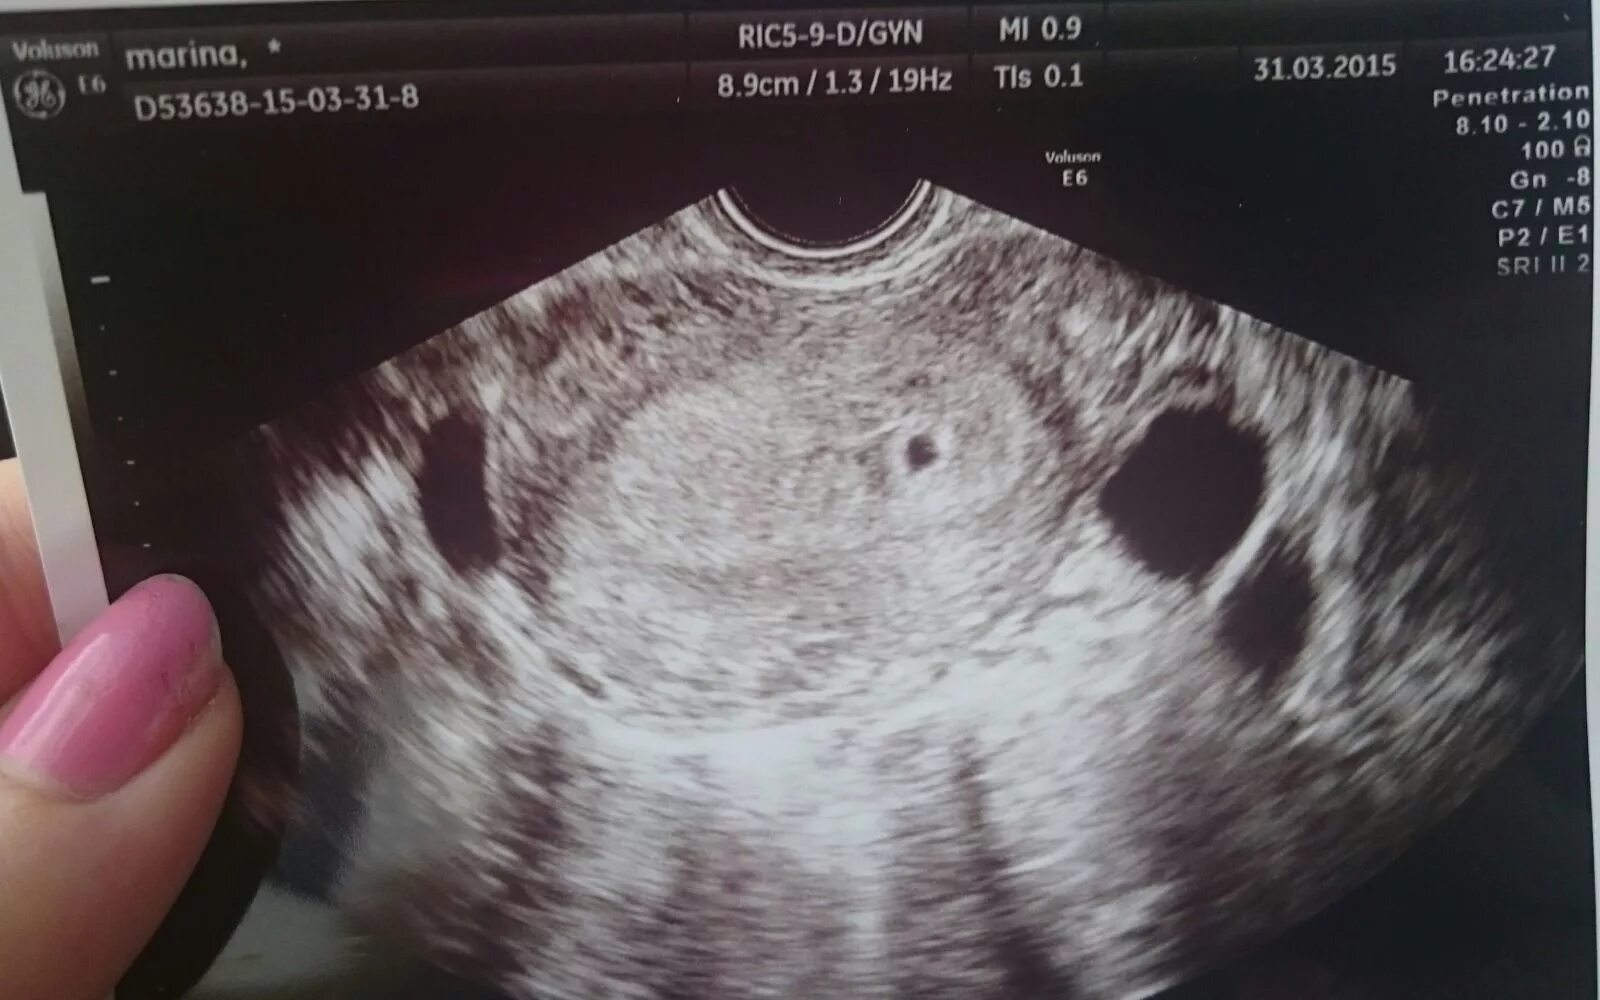

Как выглядит беременность на 1 неделе